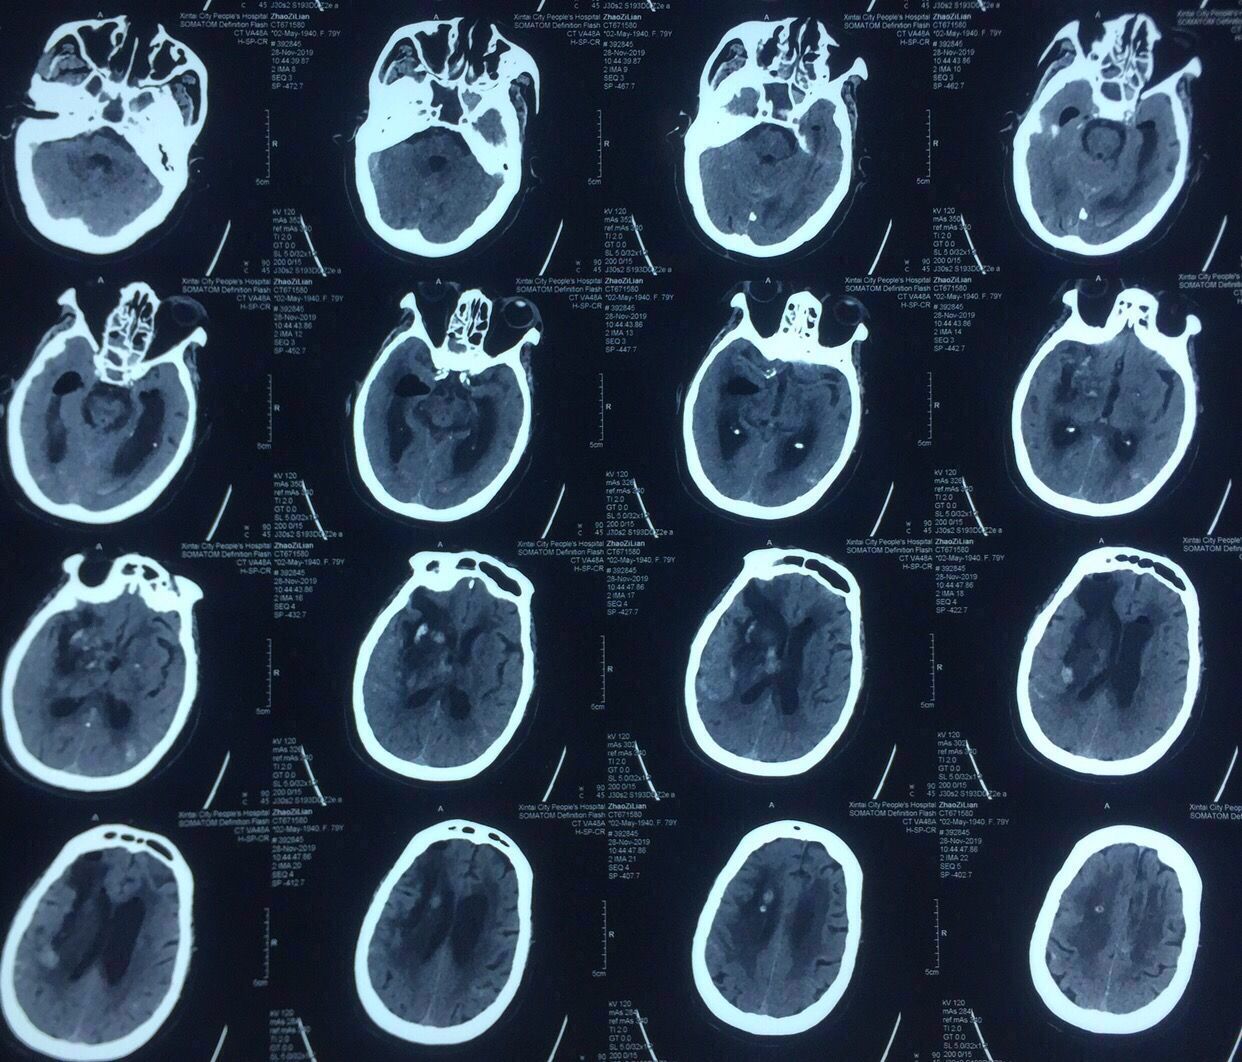

病史:女性,79岁,高血压冠心病20年,1年前脑梗死病史并脑动脉硬化、多发腔隙性脑梗死软化灶。

入院时情况:昏迷状态,血压200以上。

年龄较大,病史多,出血量大,破坏力较强,预后不良。家属不愿开颅手术,建议病情稳定行穿刺手术。

CT片见上图:

右侧基底节出血破入脑室脑积水